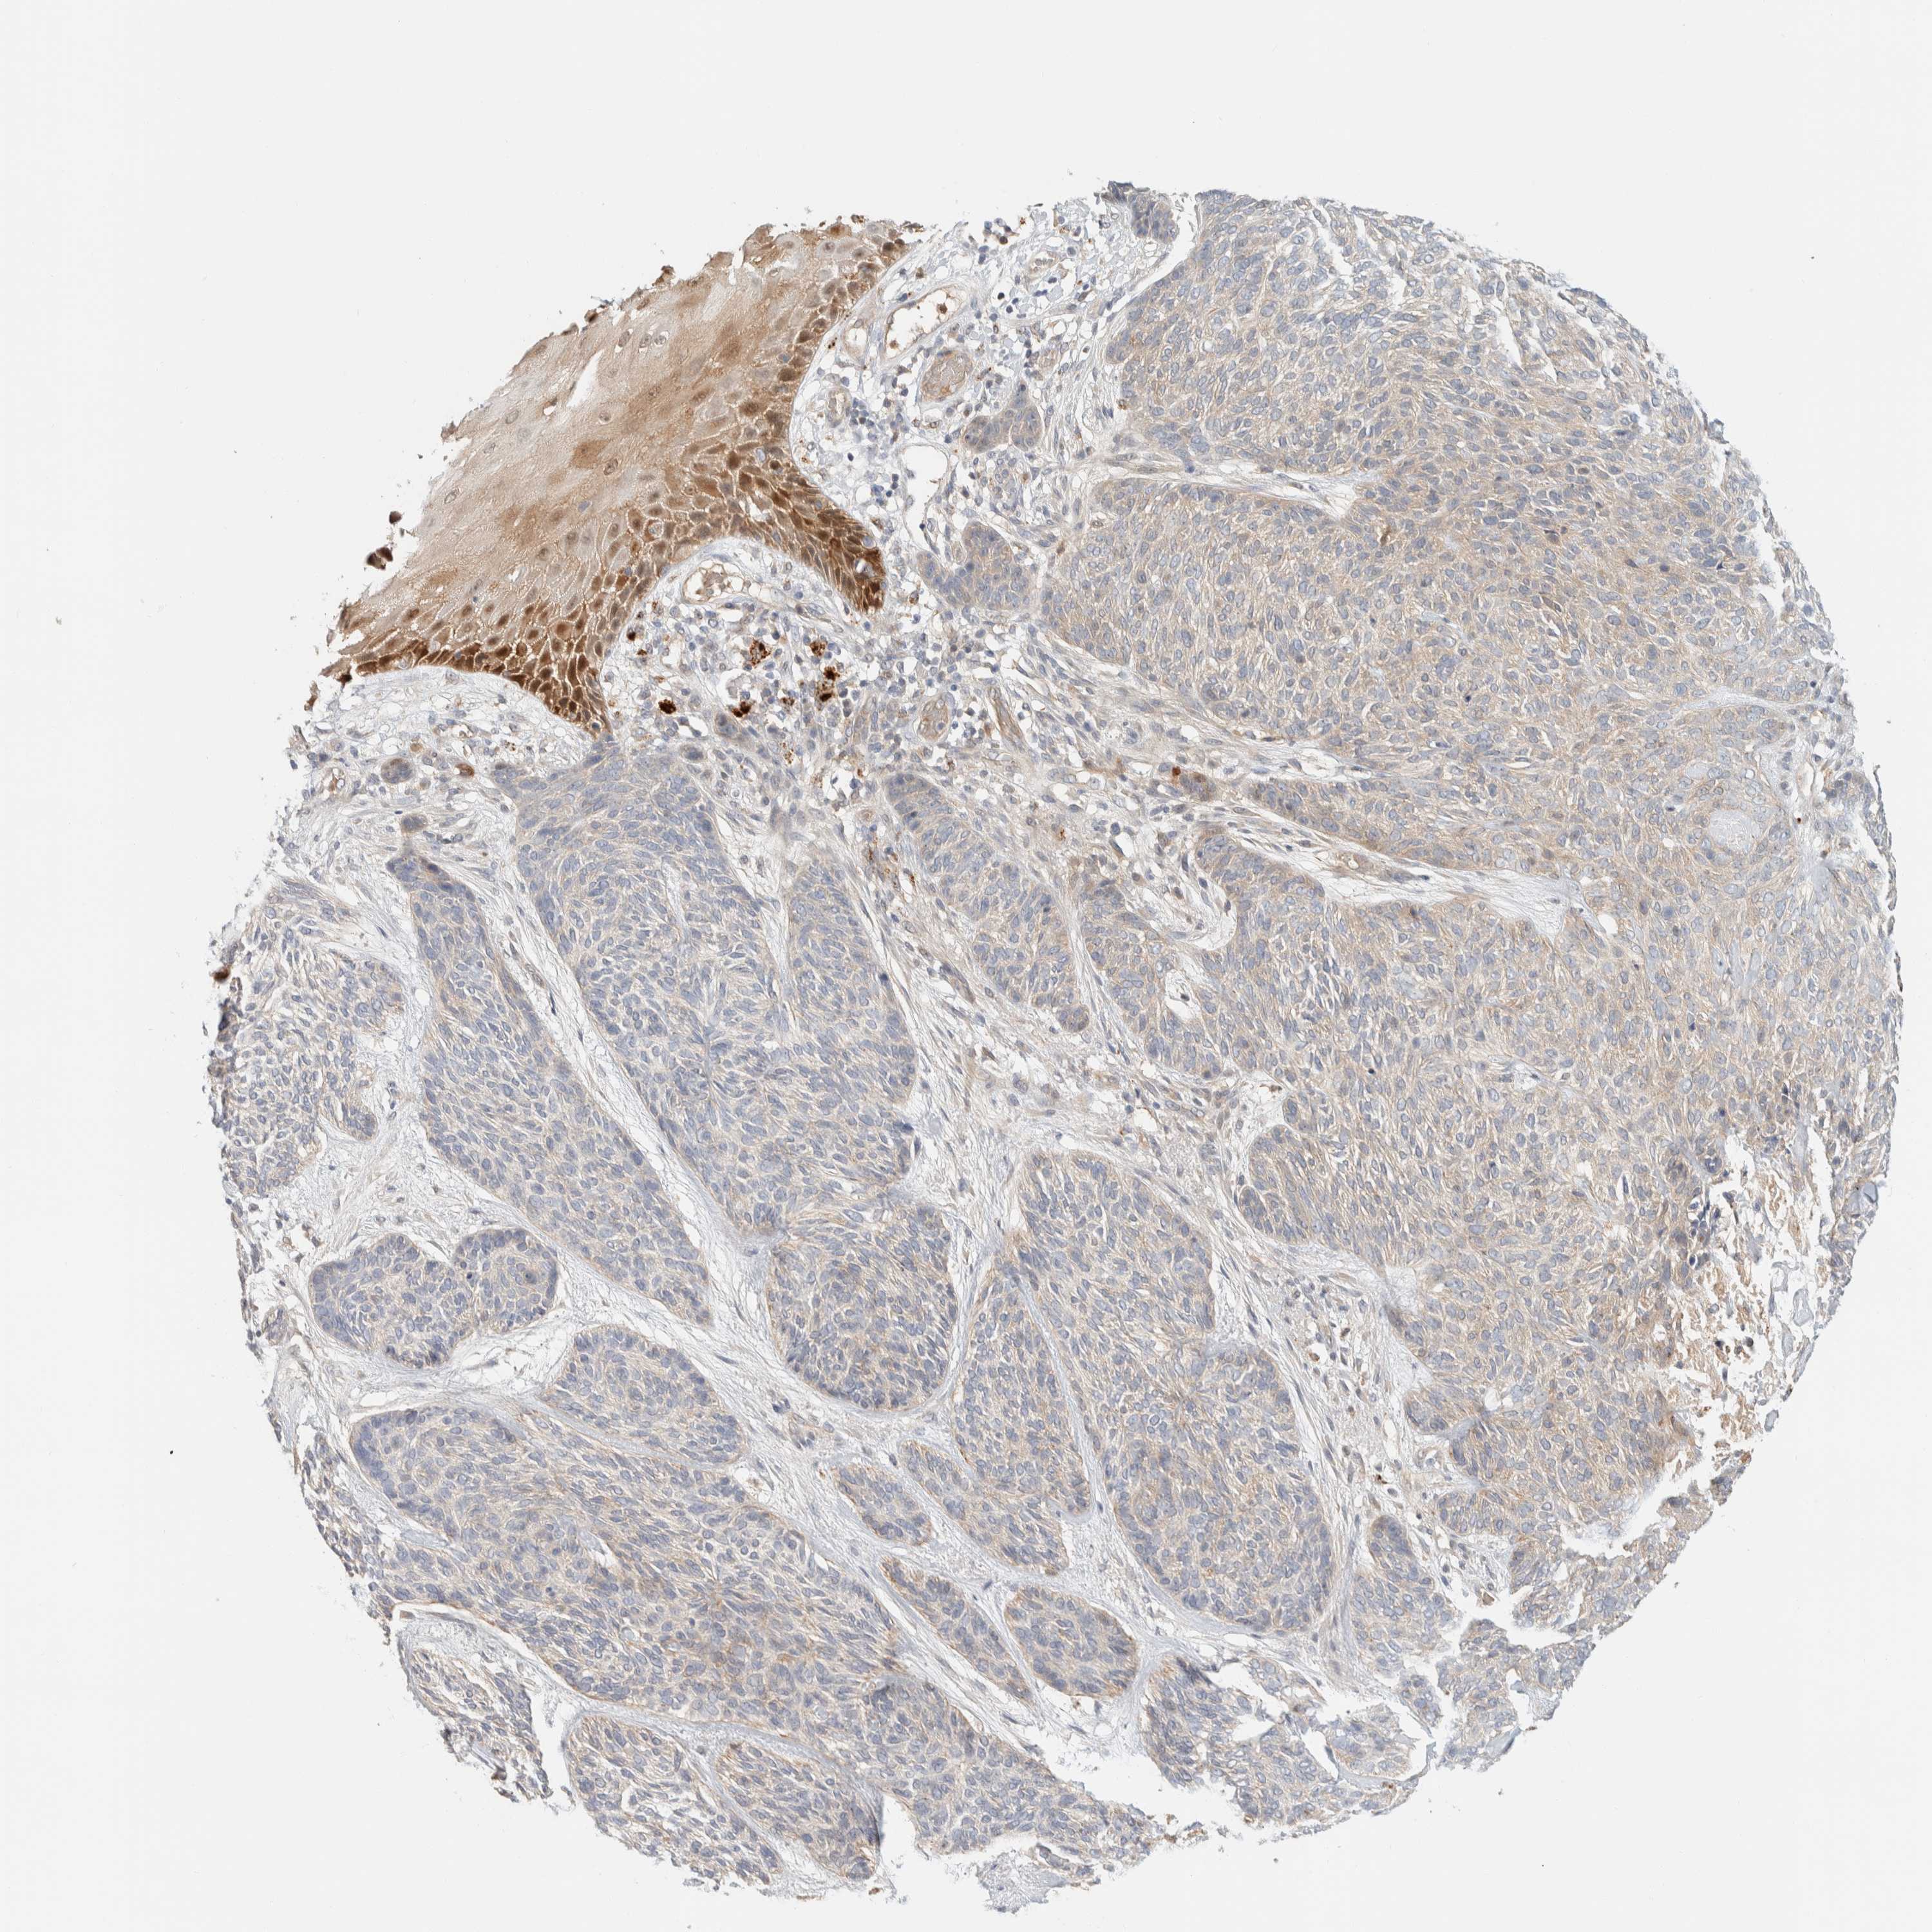

SKIN CANCER - Protein expressioni

A mouse-over function shows sample information and annotation data. Click on an image to view it in a full screen mode. Samples can be filtered based on level of antibody staining by selecting one or several of the following categories: high, medium, low and not detected. The assay and annotation is described here.

Antibody staining in the annotated cell types in the current human tissue is reported as not detected, low, medium, or high, based on conventional immunohistochemistry profiling in selected tissues. This score is based on the combination of the staining intensity and fraction of stained cells.

Each image is clickable and will lead to virtual microscopy that enables deeper exploration of all samples and also displays staining intensity scores, fraction scores and subcellular localization as well as patient and tissue information for each sample.

Basal cell carcinoma

Squamous cell carcinoma, NOS

Squamous cell carcinoma, metastatic, NOS